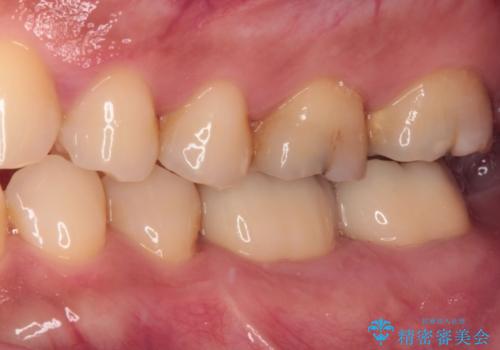

まずは仮歯に置き換え、歯周ポケットを除去するための外科処置(歯肉弁根尖側移動術)を行い、治癒を待ってセラミッククラウンにて補綴治療を行うこととしました。

外科処置後は知覚過敏症状が酷くなることが多いのですが、術後は比較的落ち着いており、スムーズに処置を進めることができました。